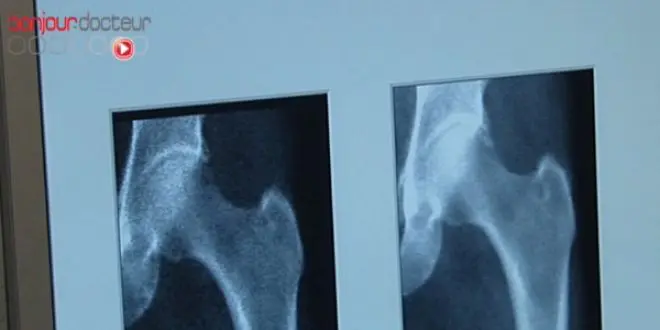

L'ostéoporose est une maladie osseuse qui associe à la fois une diminution de la densité de l'os et des modifications de son architecture interne. L'os est plus fragile et, par conséquent, le risque de fractures est important.

Col du fémur, poignets, vertèbres... l'ostéoporose est responsable chaque année de 130 000 fractures. Du fait de l'allongement de l'espérance de vie, l'ostéoporose devient un problème de santé publique, les plus âgés ne sont pas les seuls concernés et dès la cinquantaine, cette affection nous guette : près d'une femme sur deux sera victime d'une telle blessure.